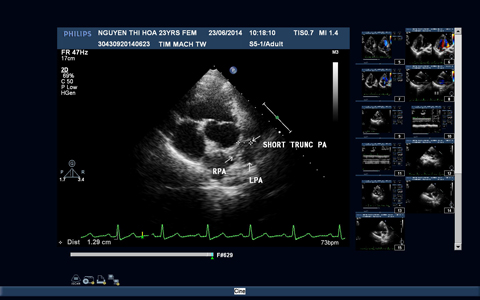

Sau phẫu thuật, hồi sức cho bệnh nhân gặp rất nhiều khó khăn do tình trạng suy thất phải gây giảm cung lượng tim. Tình trạng bệnh nhân cuối cùng đã cải thiện, các dấu hiệu suy tim phải giảm dần, SpO2 cải thiện từ 85% trước mổ lên 94%, trên điện tâm đồ nhịp xoang đều không có các rối loạn nhịp, trên siêu âm tim (Hình 3) vách liên thất kín, động mạch chủ chỉ thông thương với thất trái, ống mạch nhân tạo thông tốt, không còn ống động mạch và có hình ảnh lỗ thông liên nhĩ nhân tạo shunt trái phải và bệnh nhân đã được xuất viện.

Hình 3: Hình ảnh siêu âm tim trước và sau phẫu thuật

3A: Mặt cắt trục ngang cạnh ức trái cho hình ảnh động mạch phổi chỉ có một phần hội lưu và hai nhánh động mạch phổi.